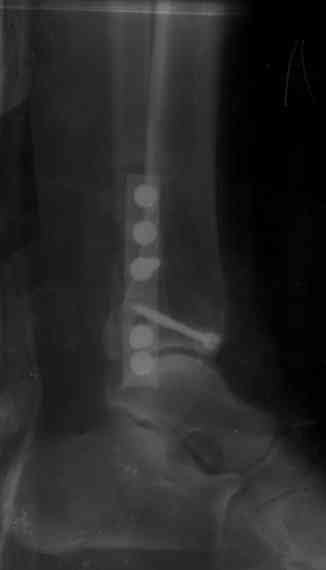

Здесь финальный снимок 73 летней с

сопутствующей шизофренией, латерально бридж

пластину (соединили дистальный конец с диафизом не трогая место перелома) и медиально перкутанно

двумя шурупами. В этам случае без гипса не

обойтись.

Джолдас, Здравствуйте,

Красивые Рг-граммы! У меня нет опыта перкутанной фиксации внутренней лодыжки, поэтому интересно узнать, наблюдали ли вы несращения внутр.лодыжки